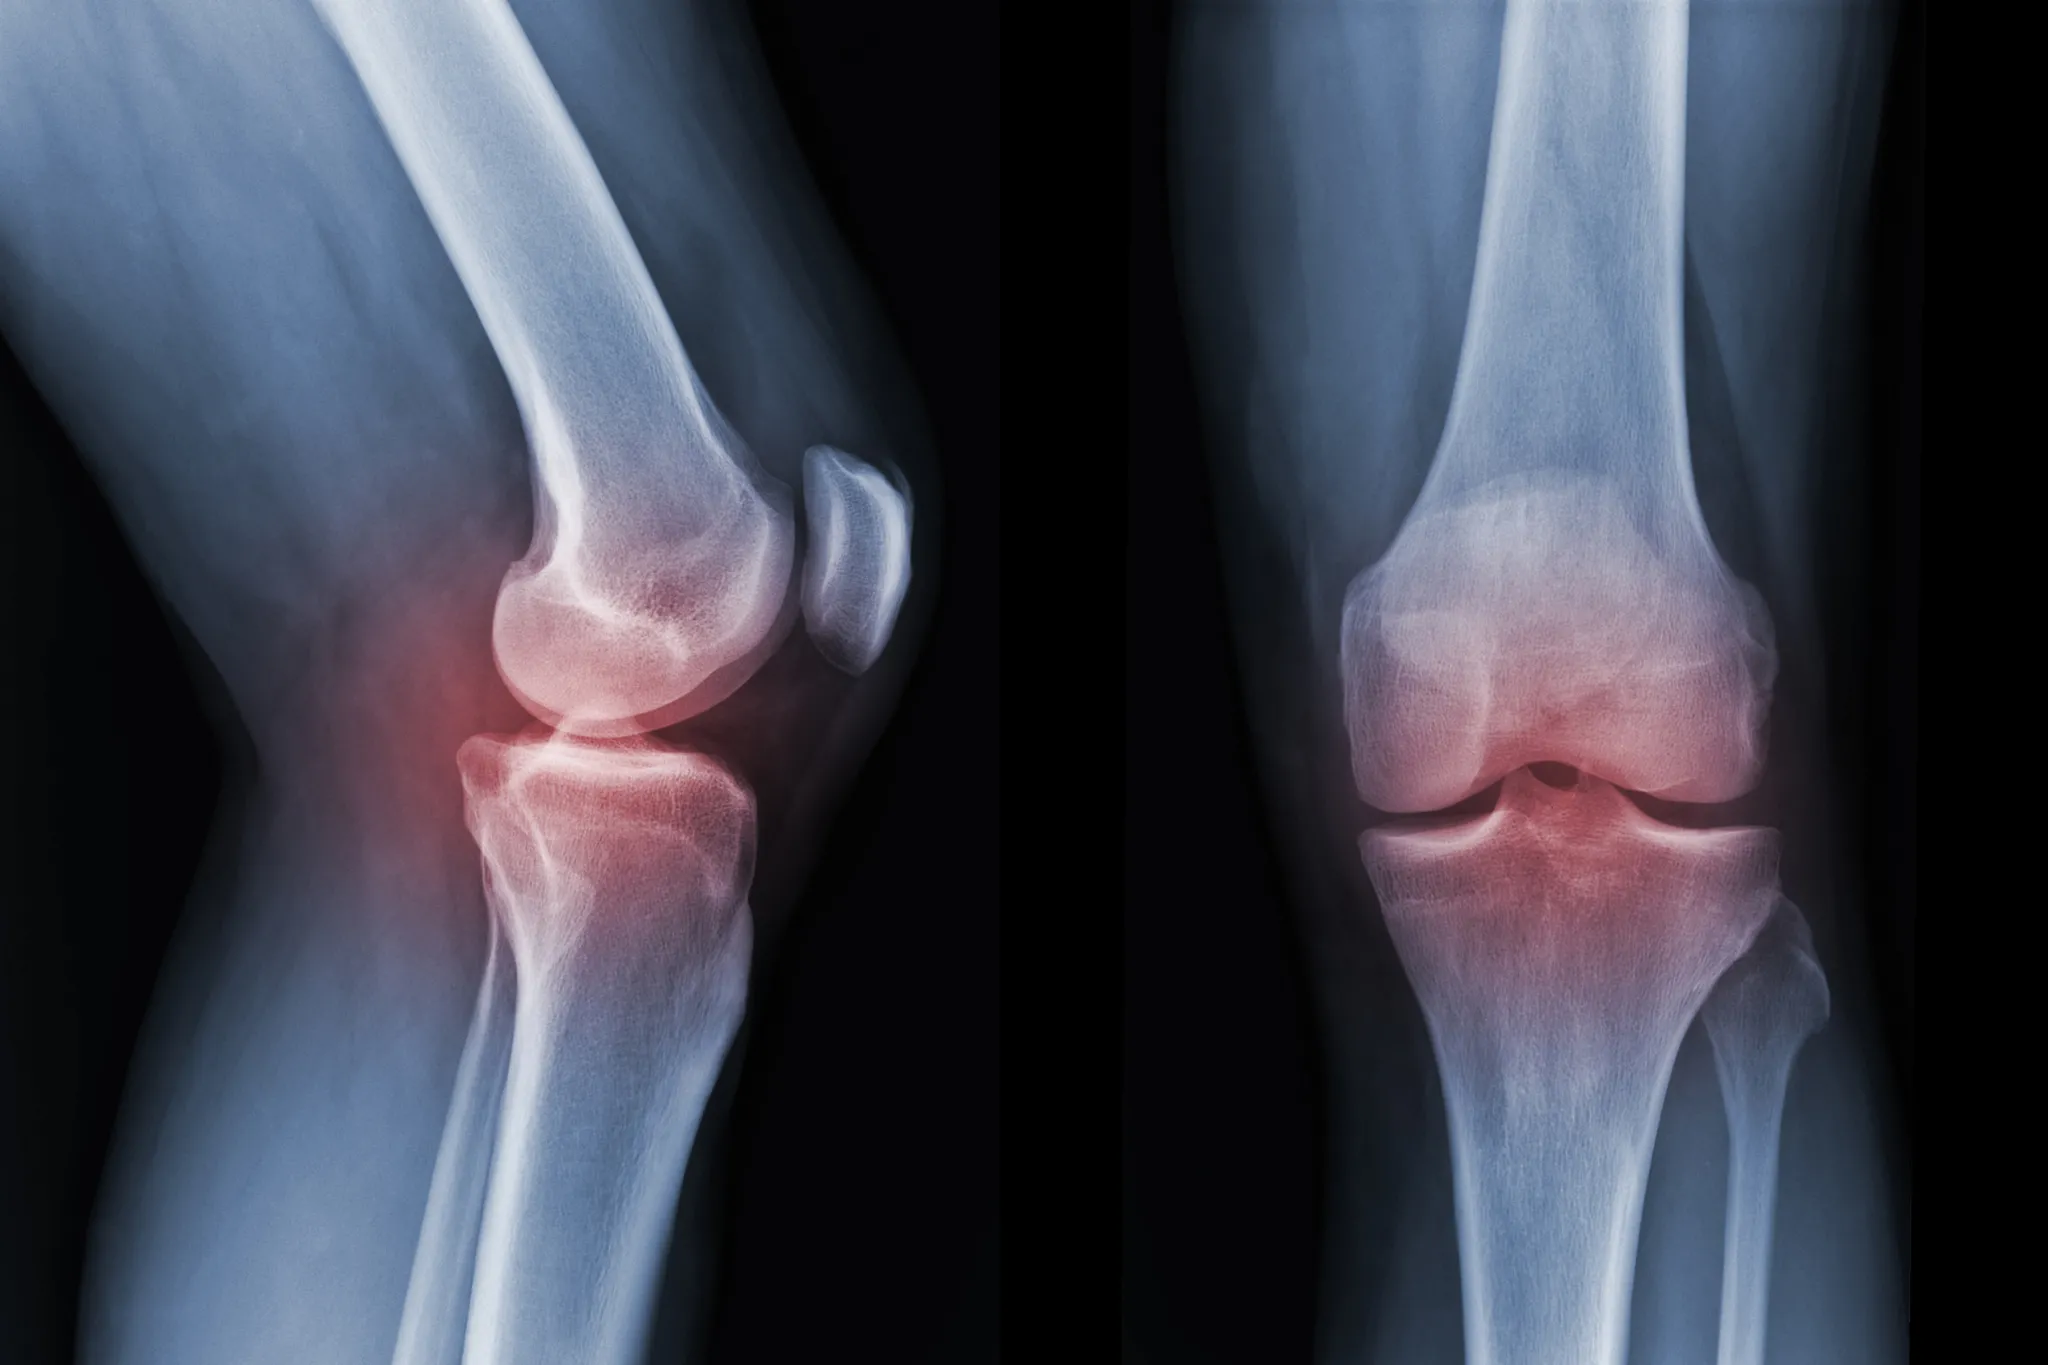

Células madre y artrosis: cómo la medicina regenerativa abre nuevas vías para mejorar la movilidad y reducir el dolor

La medicina regenerativa está generando un creciente interés en el ámbito clínico por su potencial para mejorar la recuperación de tejidos dañados. En este contexto, la relación entre células madre y artrosis está despertando un notable interés científico, ya que diferentes investigaciones exploran cómo determinadas células con capacidad regenerativa pueden participar en procesos de reparación de tejidos articulares. Una noticia reciente ha vuelto a poner el foco en este campo al mostrar cómo algunas intervenciones quirúrgicas que incorporan estas estrategias pueden contribuir a mejorar la movilidad y reducir el dolor en pacientes con artrosis.

La artrosis es una patología crónica caracterizada por el desgaste progresivo del cartílago articular. Este deterioro provoca dolor, rigidez y limitación de la movilidad, especialmente en articulaciones como rodillas, caderas o columna vertebral.